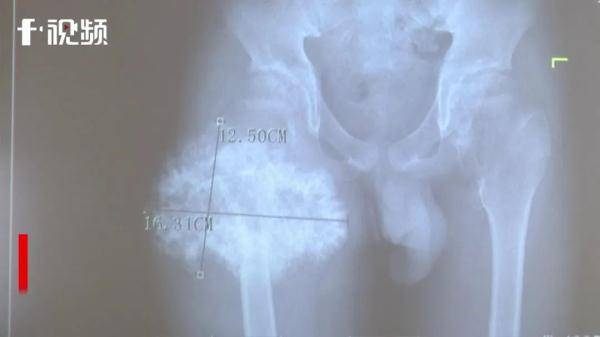

“这个孩子因为右侧大腿近端股骨上面有一个巨大的肿瘤 , 肿瘤的横径达到了将近16.5公分 , 长度达到了12.7公分左右 , 还有前后宽度有8公分左右 。 周围都是神经、血管 , 已经导致孩子的髋关节不能够弯曲 , 也不能正常旋转 。 有恶变的可能性 , 肿瘤恶变主要风险在于存在着死亡的风险 。 手术的难度就是肿瘤特别大 , 周围都是重要的神经血管 , 肿瘤紧密和骨骼连接在一起 。 ”伍江雁表示 。